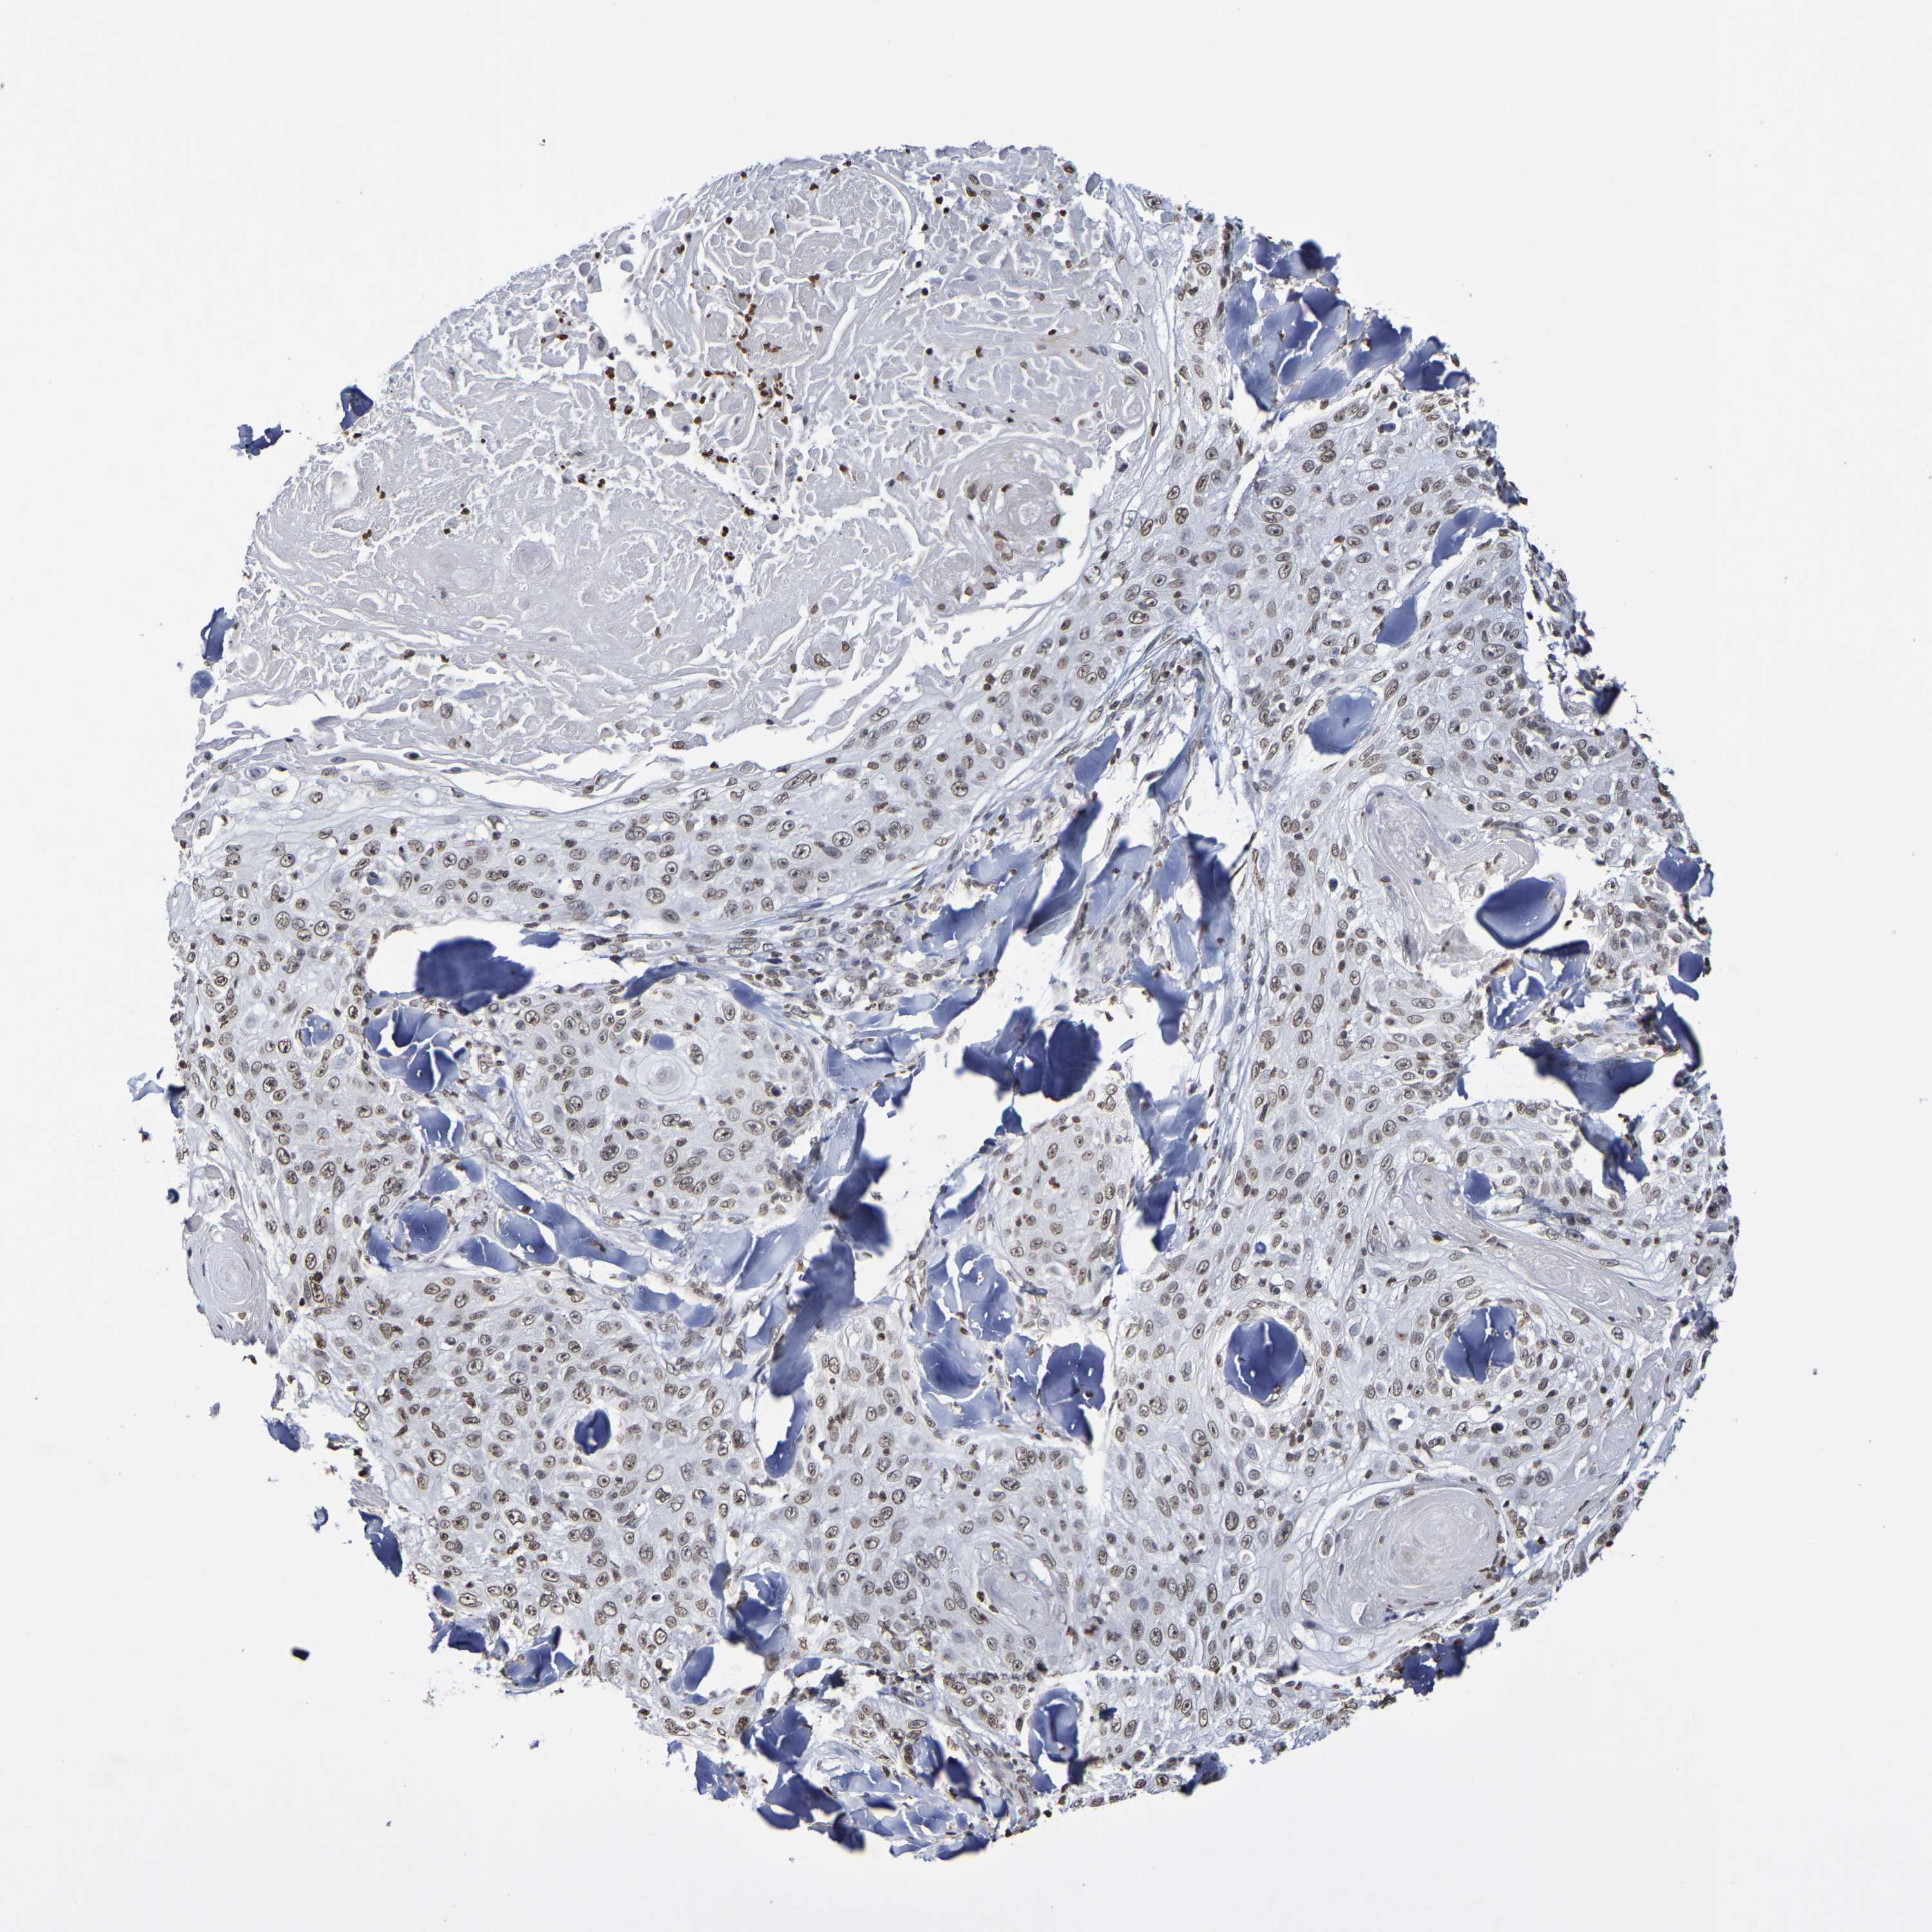

SKIN CANCER - Protein expressioni

A mouse-over function shows sample information and annotation data. Click on an image to view it in a full screen mode. Samples can be filtered based on level of antibody staining by selecting one or several of the following categories: high, medium, low and not detected. The assay and annotation is described here.

Note that samples used for immunohistochemistry by the Human Protein Atlas do not correspond to samples in the TCGA dataset.

Antibody stainingi

Antibody staining in the annotated cell types in the current human tissue is reported as not detected, low, medium, or high, based on conventional immunohistochemistry profiling in selected tissues. This score is based on the combination of the staining intensity and fraction of stained cells.

Each image is clickable and will lead to virtual microscopy that enables deeper exploration of all samples and also displays staining intensity scores, fraction scores and subcellular localization as well as patient and tissue information for each sample.

Antibody CAB011596

Staining

High

Medium

Low

Not detected

Intensity

Strong

Moderate

Weak

Negative

Quantity

>75%

75%-25%

<25%

None

Location

Nuclear

Cytoplasmic/membranous

Cytoplasmic/membranous,nuclear

Click images for details